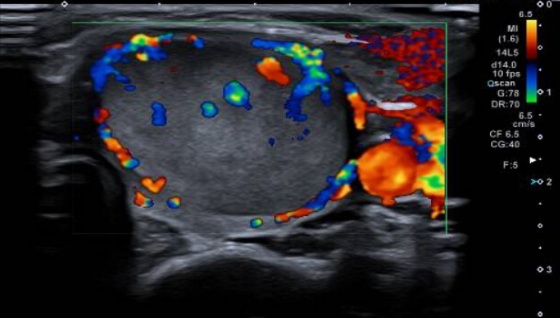

2. ECOGRAFÍA CERVICAL

Ecografía cervical: Lóbulo tiroideo izquierdo aumentado de tamaño a expensas de

imagen nodular sólida, heterogénea, predominantemente isoecoica, sin calcificaciones

y con vascularización desorganizada al examen Doppler color.